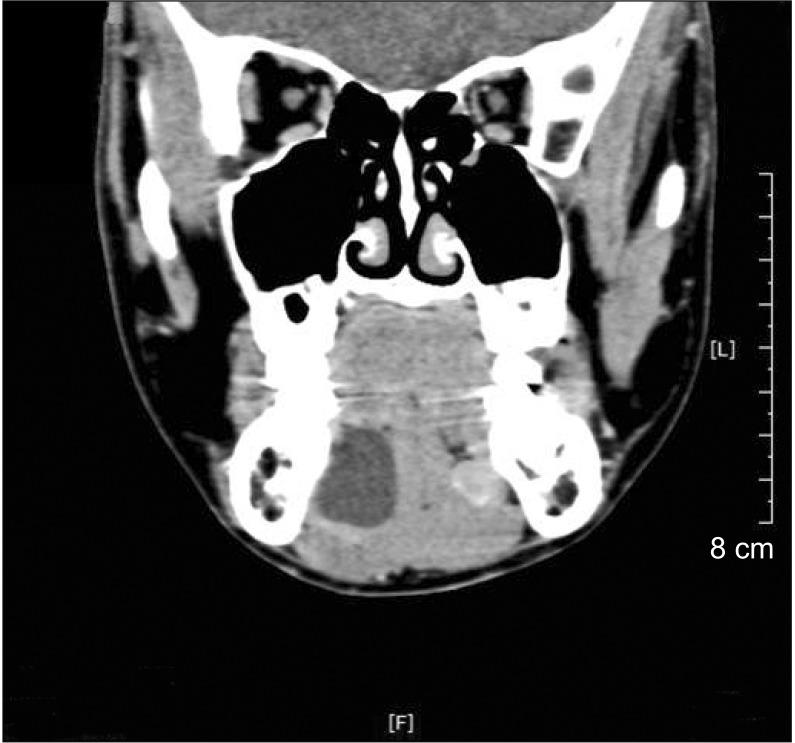

Ranula is a mucocele caused by extravasation of the sublingual gland on the floor of the mouth. The most common presentation is a cystic mass in the floor of the mouth. A portion of the sublingual gland could herniate through the mylohyoid muscle, and its extravasated mucin can spread along this hiatus into submandibular and submental spaces and cause cervical swelling. This phenomenon is called plunging ranula. A variety of treatments for ranula has been suggested and include aspiration of cystic fluid, sclerotherapy, marsupialization, incision and drainage, ranula excision only, and excision of the sublingual gland with or without ranula. Those various treatments have shown diverse results. Most surgeons agree that removal of the sublingual gland is necessary in oral and plunging ranula. Four patients with ranula were investigated retrospectively, and treatment methods based on literature review were attempted.

舌下囊肿是由舌下腺在口腔底部外渗引起的黏液囊肿。最常见的表现是口腔底部的囊性肿物。舌下腺的一部分可通过下颌舌骨肌疝出,其外渗的黏液可沿此裂隙扩散至颌下间隙和颏下间隙,导致颈部肿胀。这种现象称为舌下囊肿脱垂。已经提出了多种治疗舌下囊肿的方法,包括抽吸囊液、硬化疗法、袋形缝合术、切开引流、仅切除舌下囊肿以及切除舌下腺(伴或不伴舌下囊肿)。这些不同的治疗方法显示出了不同的结果。大多数外科医生一致认为,对于口腔内和脱垂性舌下囊肿,切除舌下腺是必要的。对4例舌下囊肿患者进行了回顾性研究,并尝试了基于文献综述的治疗方法。